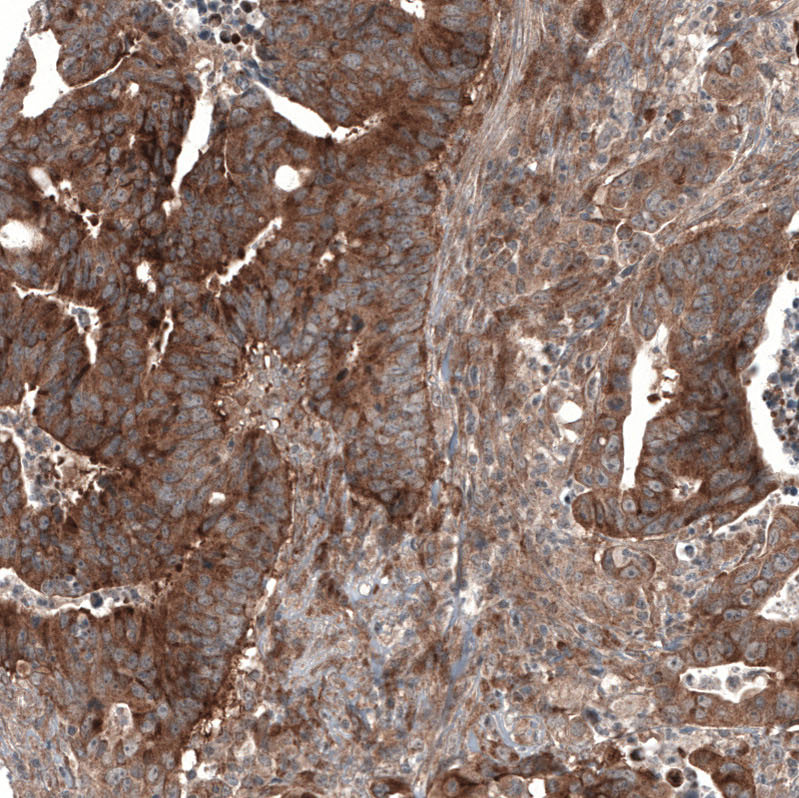

Immunohistochemical staining of human breast cancer shows strong cytoplasmic positivity in tumor cells.